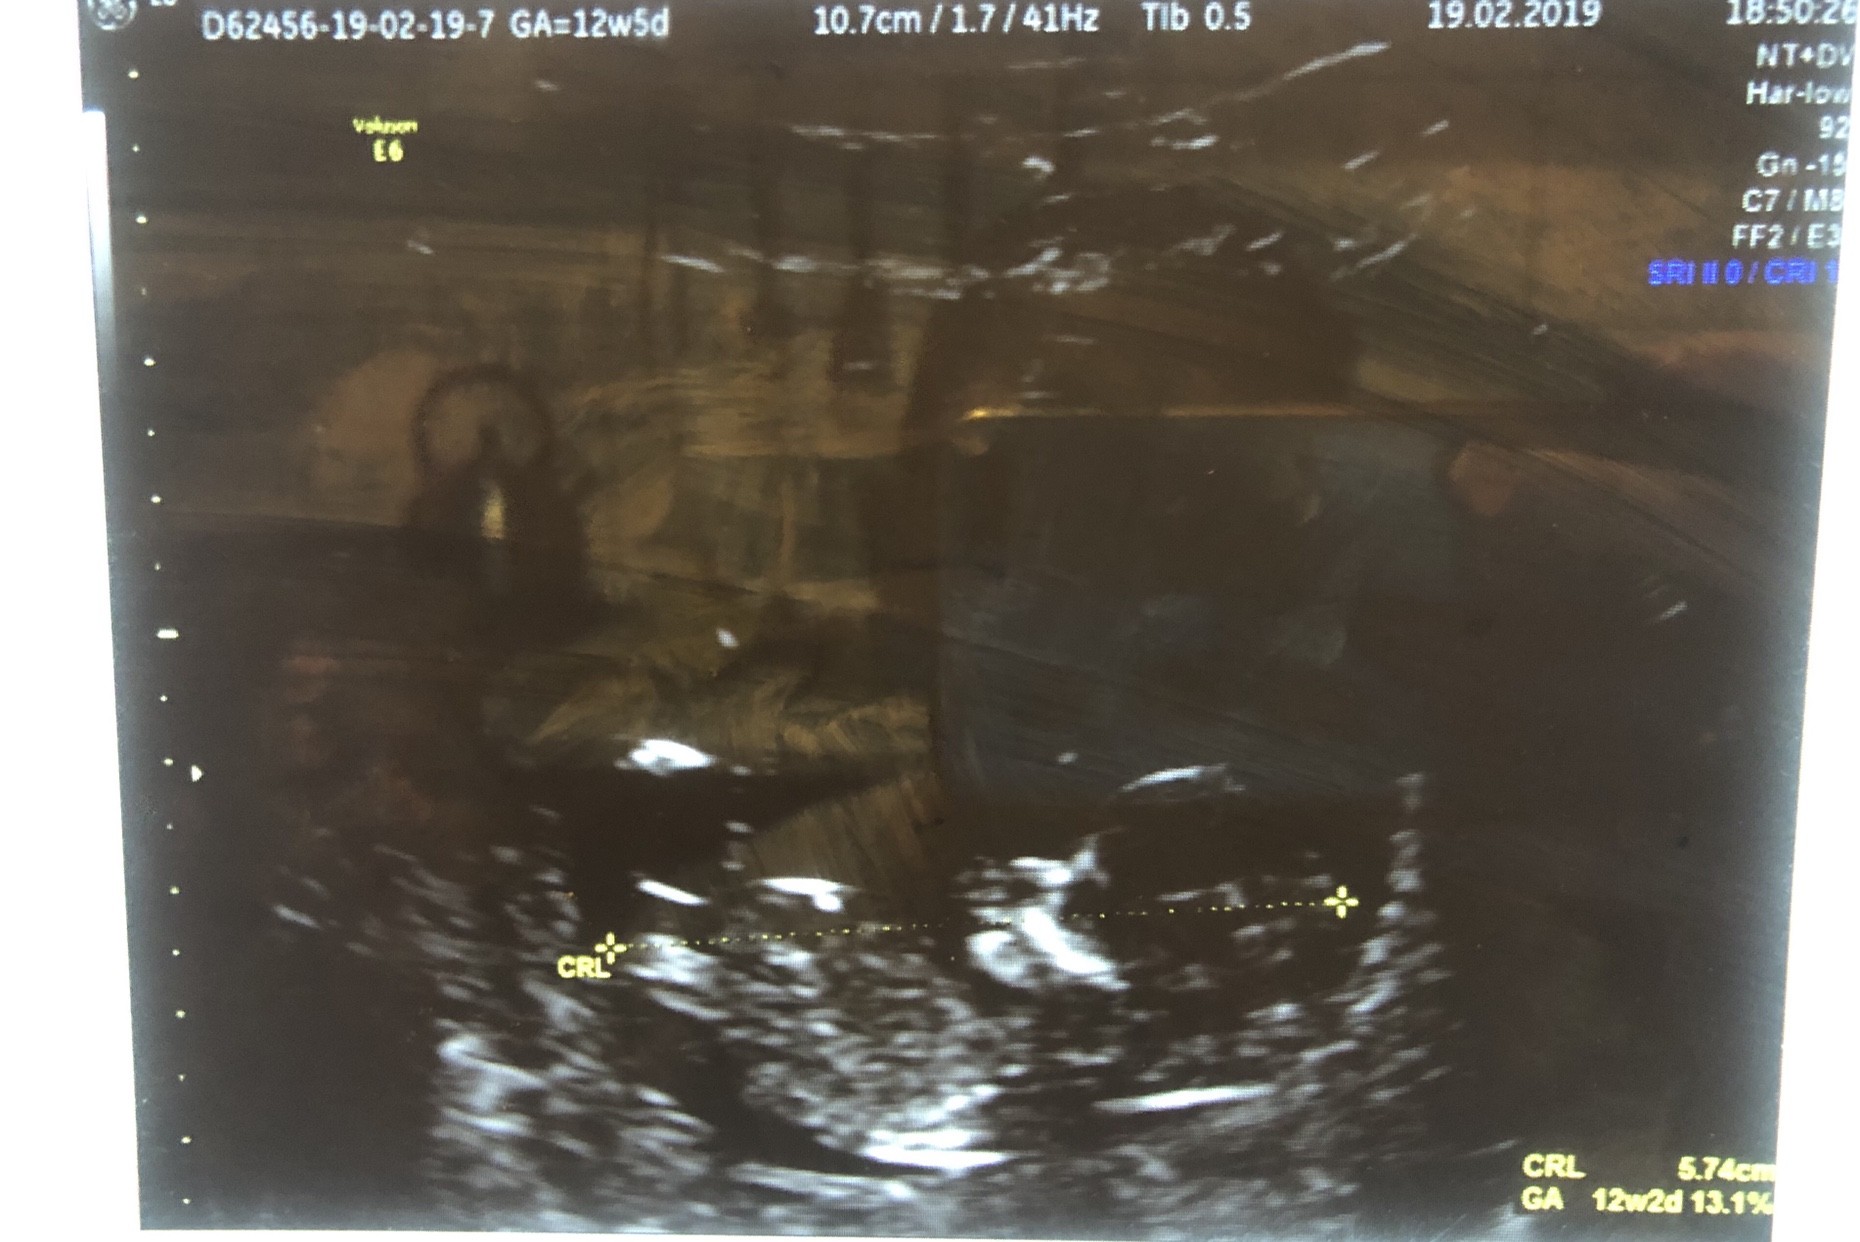

IMG_3300.JPG

Nasza fasolka [emoji7] 5,7 cm miłości.